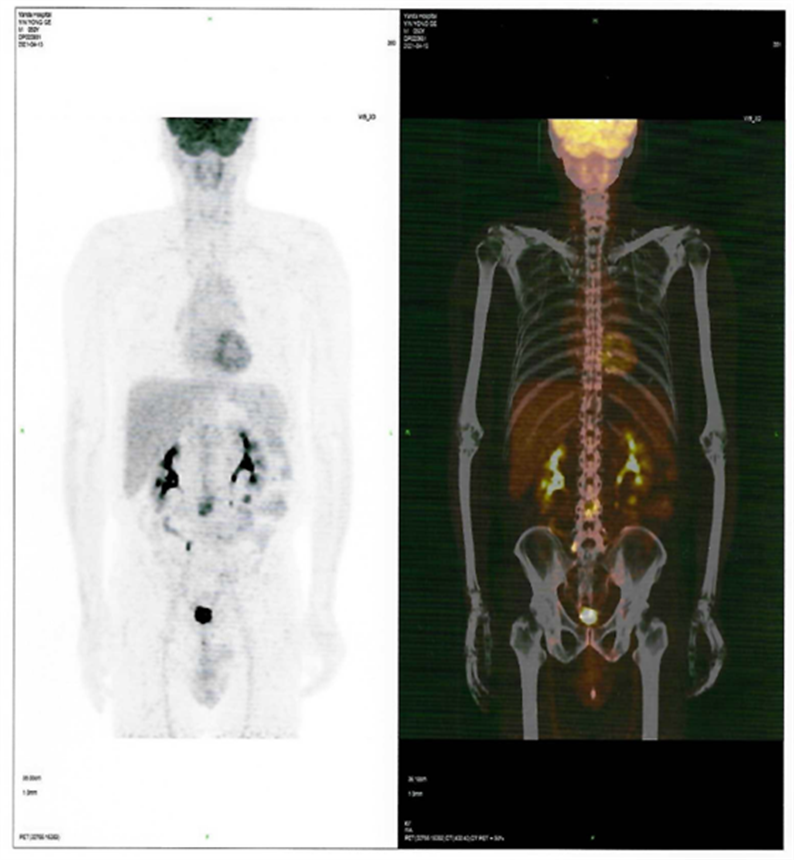

近日,燕達(dá)陸道培醫(yī)院血液科二病區(qū)傳來(lái)好消息,一位罹患T細(xì)胞淋巴瘤前期在美國(guó)治療復(fù)發(fā)的患者,428日,在我院回輸CD7 CAR-T細(xì)胞,526日經(jīng)PET-CT檢查,顯示CR(完全緩解)。

患者CAR-T 前后PET-CT檢查結(jié)果對(duì)比圖

CAR-T治療前

CAR-T治療后30

2021412日,患者來(lái)到燕達(dá)陸道培醫(yī)院,希望借助我院的CD7 CAR –T臨床試驗(yàn)項(xiàng)目獲得一線生機(jī)?;颊叱跞朐簳r(shí)PET-CT檢查提示:腫瘤細(xì)胞累及多處腸系膜和腹部肌肉軟組織;骨髓未累及。

回輸后一度出現(xiàn)了一級(jí)CRS反應(yīng),癥狀可控,526日,回輸后+28天復(fù)查PET-CT顯示CR(完全緩解)。預(yù)祝黃山先生接下來(lái)的治療一切順利!